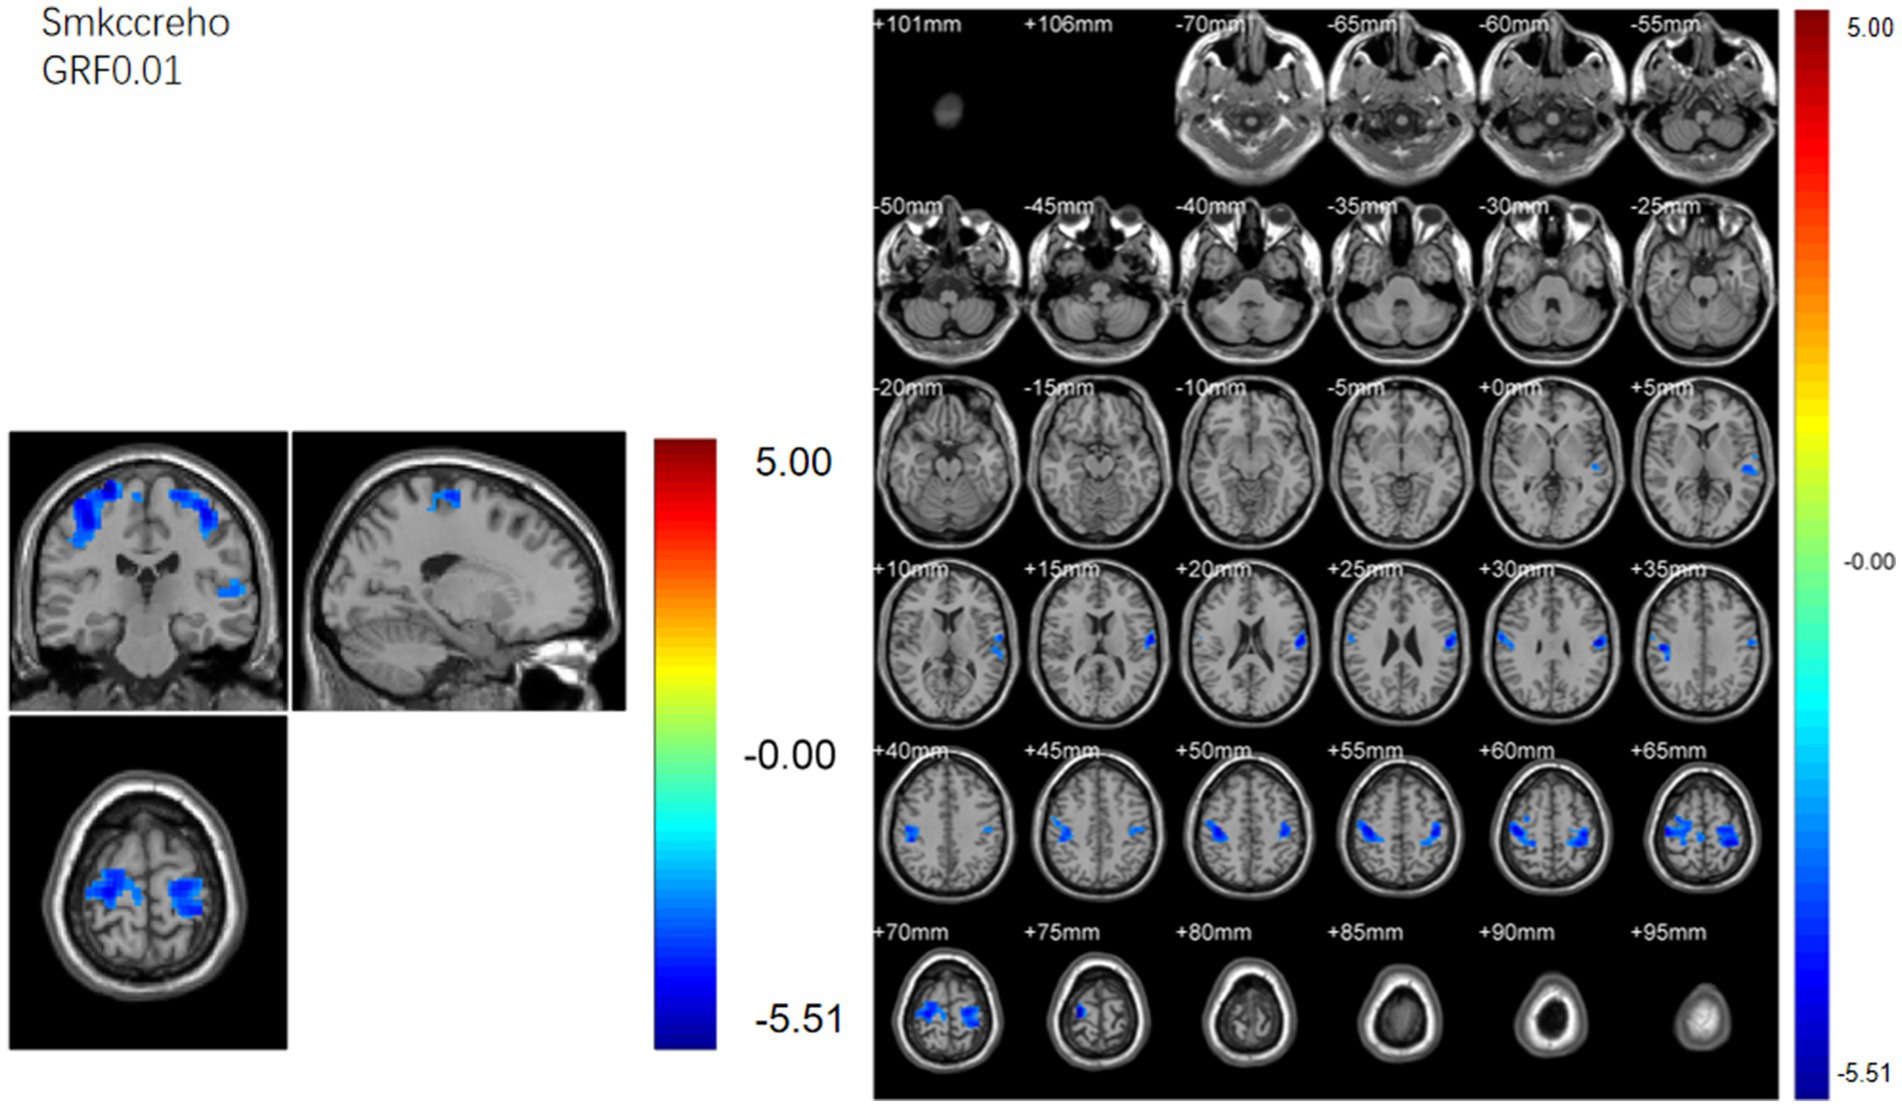

ABSTRACT Background: Spinal diseases related pain represents a critical clinical issue that demands urgent resolution. Current treatment and assessment strategies predominantly focus on peripheral mechanisms. The application of functional magnetic resonance imaging (fMRI) offers a promising approach to identifying potential central targets for intervention. Methods: We retrospectively included 31 patients with spinal diseases related pain and 32 controls with non-spinal, orthopedic complaints (no chronic neurological or psychiatric disorders). All participants underwent resting-state brain fMRI (eyes closed, awake). We quantified amplitude of low-frequency fluctuations (ALFF) with mean normalization (mALFF) and z-transformation (zALFF), regional homogeneity (ReHo; 27-voxel neighborhood), seed-based functional connectivity (FC; pre/postcentral seeds), and degree centrality (DC; binary and weighted). Between group tests used voxel-wise two-sample t_tests with Gaussian Random Field (GRF) correction. Results: Patient group was associated with increased m/zALFF in right cerebellar lobule IX and right Superior Frontal Gyrus, medial part , and lower activity in bilateral postcentral gyri and the Cuneus. , decreased m/zALFF in bilateral postcentral gyri. ReHo analysis confirmed reduced local synchrony in postcentral regions , spatially overlapping with ALFF findings. FC analyses revealed enhanced cerebellar-thalamic connectivity (Crus1/2, thalamus) but reduced connectivity in sensorimotor and higher-order cortical networks. DC showed hyperconnectivity in left cerebellar Crus I with reduced Superior Frontal Orbital (Frontal_Sup_Orb). All findings survived GRF correction at the pre_specified thresholds. Conclusions: Resting-state brain fMRI indicates a cerebello-thalamo-cortical alteration pattern in spinal diseases related pain featuring cerebellar involvement, prefrontal subspecialization, and multilevel sensorimotor disruption. These cross-sectional associations may inform hypothesis-generation for future neuromodulation studies and provide candidate biomarkers for monitoring, pending prospective validation.